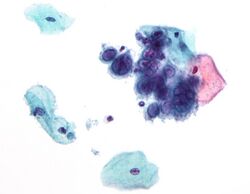

Micrograph of a pap test showing changes (upper right of image) associated with herpes simplex virus, a vertically transmitted infection

Some vertically transmitted infections, such as toxoplasmosis and syphilis, can be effectively treated with antibiotics if the mother is diagnosed early in her pregnancy. Many viral vertically transmitted infections have no effective treatment, but some, notably rubella and varicella-zoster, can be prevented by vaccinating the mother prior to pregnancy.[citation needed]

If the mother has active herpes simplex (as may be suggested by a pap test), delivery by Caesarean section can prevent the newborn from contact, and consequent infection, with this virus.[citation needed]